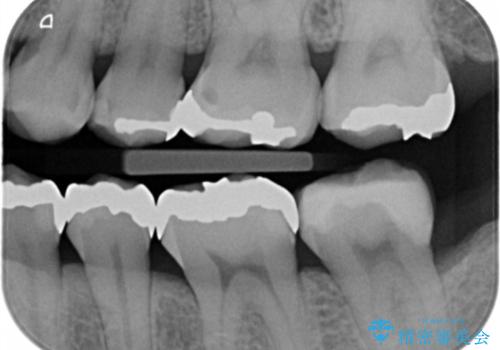

- 銀の詰め物が目立ので白くしたいとの事で来院。

とりあえず奥の二つから白くしたいとの事だったので

銀の詰め物を外し、e-maxインレーにしました。

e-maxインレーは銀の詰め物に比べ歯との隙間ができにくく

虫歯の再発リスクが少ないです。